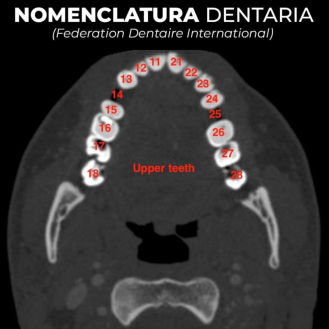

Formado por: boca, faringe, esófago, estómago, intestino delgado, intestino grueso, recto y ano. Su pared está compuesta de 3 capas: Una capa muscular longitudinal. Una capa muscular circular. Una capa interna de tejido epitelial o mucosa, con glándulas que producen mucus y jugos digestivos. Las capas musculares le dan elasticidad y movilidad (peristalsis). LA BOCA Orificio de entrada al digestivo. Cerrada por los labios. En su interior está la lengua, órgano muscular que ayuda a la masticación, deglución y percepción de sabores. La boca se comunica con la faringe o garganta, común a digestivo y respiratorio. DIENTES Los dientes son las partes más duras del cuerpo humano. Se encuentran alojados en cavidades de la mandíbula llamadas alveolos y unidos a las encías. Un diente tiene las siguientes partes: Existen cuatro tipos de dientes: Incisivos: (paletas). Corona plana y afilada. Sirven para cortar los alimentos. Caninos: con corona puntiaguda. Para desgarrar. Premolares: de corona ancha y aplanada. Para aplastar y triturar Molares: de igual forma y función que los premolares, pero mayores y con 3 raíces. Los humanos tienen dos denticiones. La primera aparece a los 6 meses y dura hasta los 6 años. Consta de 20 dientes (todos menos los molares). Es la llamada dentición de leche. La 2ª aparece a partir de los 6 años, sustituyendo a la anterior y añadiendo los molares, con lo que consta de 32 dientes. Es la dentición definitiva. FARINGE Garganta. Cavidad común al digestivo y al respiratorio. ESÓFAGO Tubo de 25 cm. Conecta la boca y el estómago, atravesando el diafragma. Se halla entre la tráquea y la columna vertebral. ESTÓMAGO Órgano en forma de saco. Capacidad de litro y medio. Tiene un orifico de entrada (cardias), comunicado con el esófago y controlado por un esfínter (músculo circular) y otro de salida (píloro), que lo comunica con el intestino delgado gracias a otro esfínter. La pared interna tiene una mucosa protectora y glándulas que fabrican el jugo gástrico. El estómago almacena el alimento y lo digiere en parte, controlando su paso al intestino. INTESTINO DELGADO Tubo largo y delgado, de unos 5 metros, por lo que se halla enrollado en el abdomen. Se divide en tres partes: Duodeno: primer tramo. Unos 25 cm. A él vierten los conductos biliares y pancreáticos. Yeyuno: parte media. En él se da principalmente la absorción. Íleon: porción final, y más larga, del intestino, donde se acaban de absorber los nutrientes. Desemboca en el intestino grueso por la válvula ileocecal. La pared del intestino delgado está muy plegada para aumentar su superficie de absorción. Además, estos pliegues presentan otros menores con forma de dedo llamados vellosidades, cuyas células tienen repliegues de la membrana denominados microvellosidades. De esta forma se consigue una superficie total de varios m 2 . INTESTINO GRUESO Tubo más grueso y corto que el intestino delgado. Mide 1,5 m y unos 10 cm de grosor. Se divide en: Ciego: primera porción, con forma de fondo de saco y con una prolongación de unos 7 cm llamada apéndice vermiforme. Colon: parte más larga, con forma de ‘U’ invertida. presenta una porción ascendente, una transversa y una descendente. Recto: última porción. Acumula las heces antes de su salida al exterior. ANO Orificio de salida del digestivo, situado al final del recto, y controlado por el esfínter anal. A través de él se expulsan las heces al exterior.